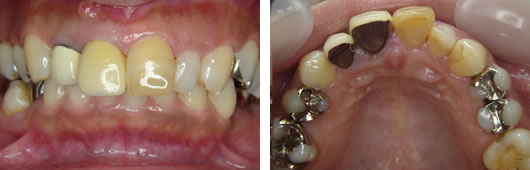

40代女性

治療前

治療後